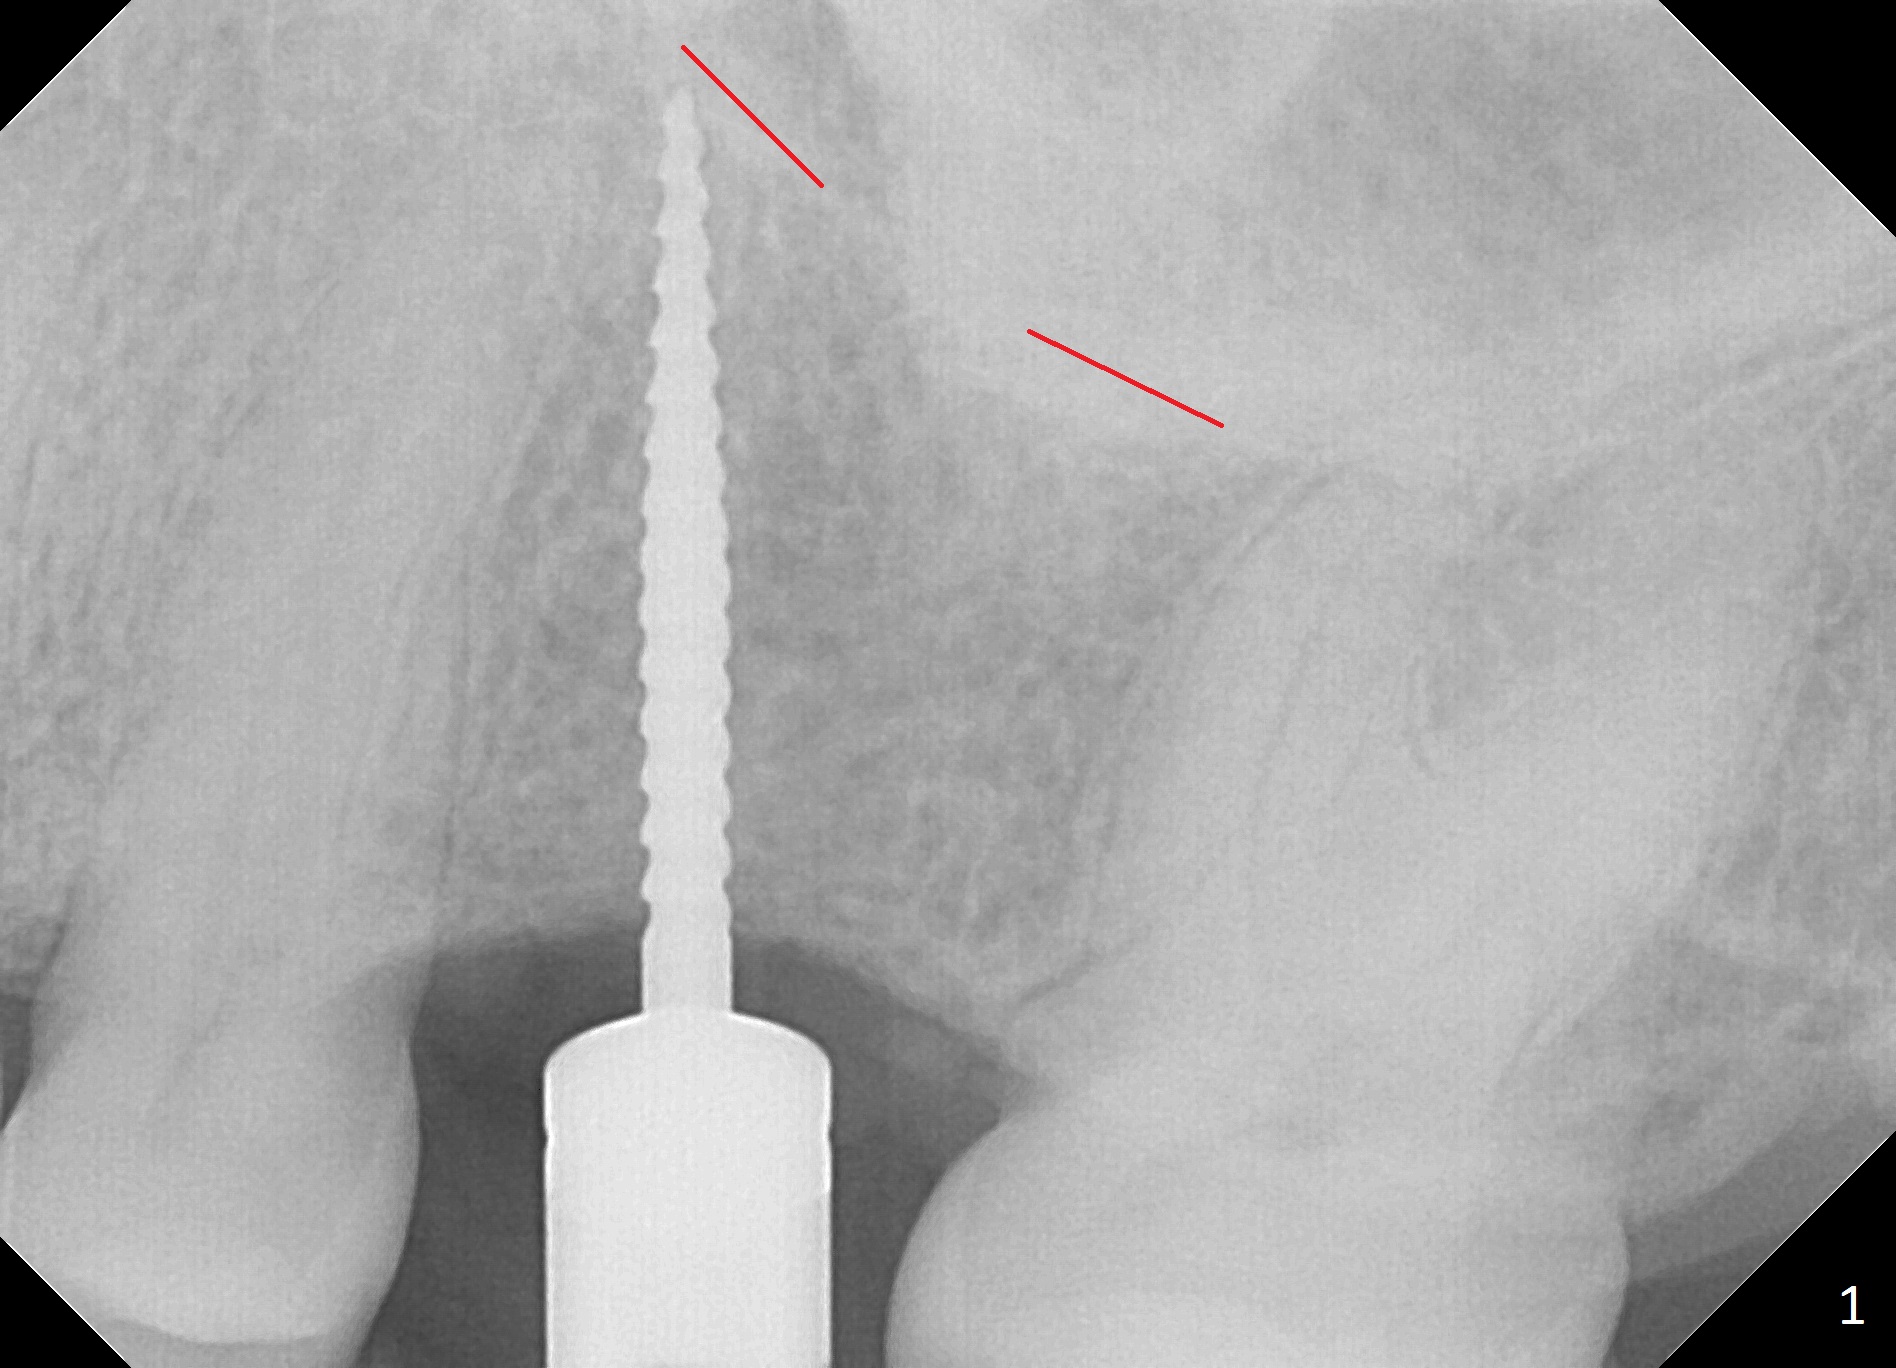

The edentulous area at #14 is moderately atrophic, After incision, the bone is too hard for #15 blade for bone expansion. Osteotomy is initiated with 1.2 mm drill, followed by insertion 1.3/2.3 mm bone expander (Fig.1). Use the same instruments are reused twice to change the trajectory (Fig.2,3). Finally Lindamann bur is utilized to move the osteotomy distally by ~ 2 mm; bone expansion continues until 2.4/3.7 mm expander for 13 mm with 50 Ncm (Fig.4). The last expander 3/4.4 mm barely enters the osteotomy for 6 mm. A 3.7 mm drill has to be used for 12 mm before placement of a 4.5x11.5 mm implant with >35 Ncm (Fig.5). A 5.5x5(3) mm abutment is placed with allograft (<) placed around the implant. Following suturing, periodontal dressing is applied around the implant. The abutment dislodges 3 months postop (Fig.6). Crown is delivered 3 weeks later. The abutment screw is retightened ~ 2 months later. He is a bruxer. The abutment screw is loose again <2 years post cementation (6 months post #18 screw retightenting and occlusal reduction), probably related to distal implant placement (Fig.7).